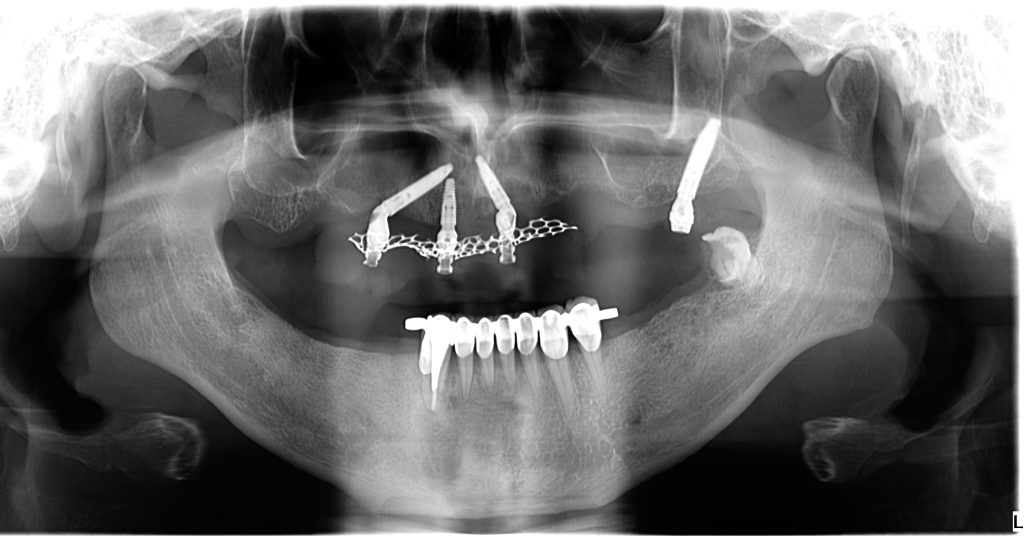

Pterygoid implant as a rescue implant replacing the failing distal implant in All on 4 restoration